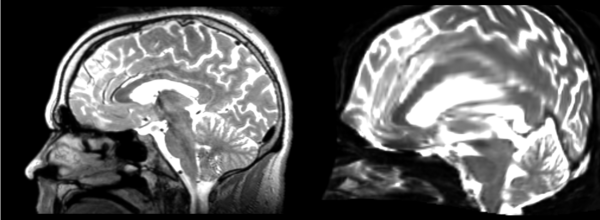

Affine

- 53-t2 -> 31-t1 = aff1

- aff1 -> 53-t2 = aff2

The image shows these side by side. The are nearly the same except for the loss of fine detail.

Linear

- 53-t2 -> 31-t1 = lin1

- lin1 -> 53-t2 = lin2

The image shows lin2 and 53-t2 side by side. The image shows there appears to be some change beyond loss of detail, possibly a L-R shift in the front.